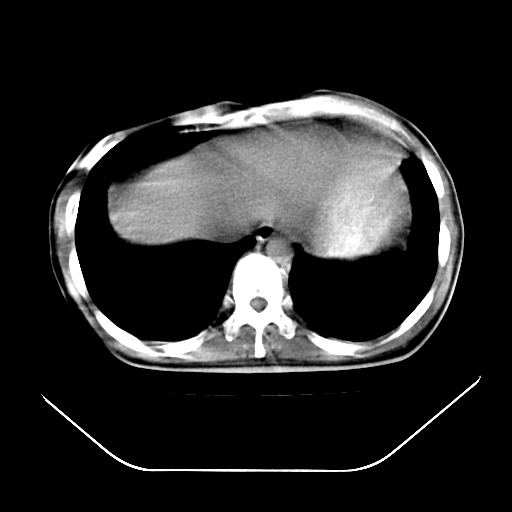

以下是引用深泽交通医院在2008-7-17 12:05:00的发言:[br]肝门淋巴结肿大;胆结石

以下是引用文莱在2008-7-17 16:32:00的发言:[br]胆囊结石 余未见异常

以下是引用随光逐影在2008-7-17 17:52:00的发言:[br]1)胆囊结石。2)肝门及胰头区淋巴结肿大可能(原因不明);建议行进一步检查。

以下是引用卜一在2008-7-17 16:37:00的发言:[br]支持胆囊结石!!!至于胰头区病变——建议强化后再定论!